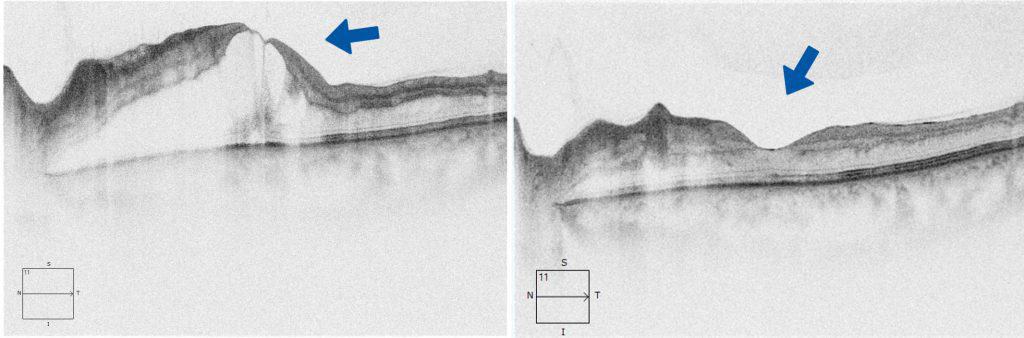

Diese Schwellung, die mithilfe eines modernen hochauflösenden OCT diagnostiziert werden kann, führt zu einer Verschlechterung der zentralen Sehschärfe. Durch die Eingabe eines entsprechenden Medikaments in das Augeninnere (intravitreale Injektion) kann diese Veränderung behandelt oder zumindest stabilisiert werden. Es können allerdings wiederholte Eingaben dieser Medikamente erforderlich werden.